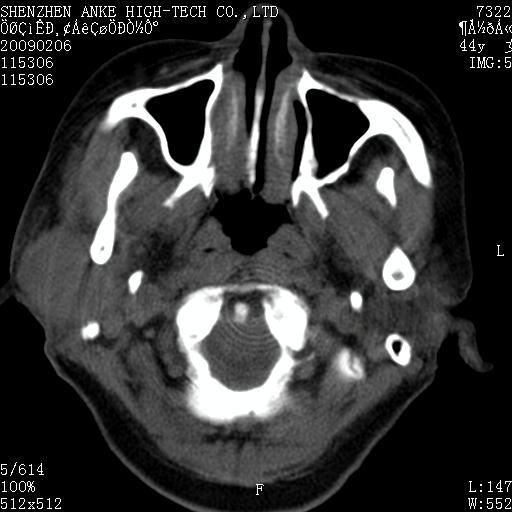

标题: CT17977:女,44岁,右侧颌部包块1年,右侧面瘫2月。 [打印本页]

患者:女,44岁,右侧颌部包块1年,右侧面瘫2月。

考虑右侧腮腺混合瘤可能性大

考虑右侧腮腺混合瘤。

考虑右侧腮腺混合瘤。年轮样伪影考虑机器问题!

考虑右侧腮腺混合瘤;不排除腮腺癌。

右侧腮腺肿瘤,良恶性难定。